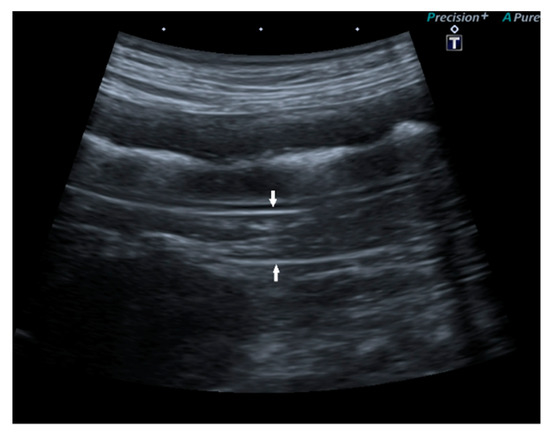

Successful Management of a Pancreatic Abscess in a Dog with Juvenile Diabetes Mellitus Through Ultrasound-Guided Drainage and Medical Therapy

by Alexandra Daravigka, Stefanos Ninis, Panagiotis Bourdekas, Alexandros O. Konstantinidis, Argyrios Ginoudis, Katerina K. Adamama-Moraitou, Maria Lyraki and Nektarios Soubasis

A five-month-old female mixed-breed dog presented with a two-week history of polyuria, polydipsia, and vomiting. Clinical examination revealed poor body condition, growth retardation, pale oral mucous membranes, weak pulse, and prolonged capillary refill time. Laboratory findings included neutrophilic leukocytosis with a regenerative left [...] Read more.

A five-month-old female mixed-breed dog presented with a two-week history of polyuria, polydipsia, and vomiting. Clinical examination revealed poor body condition, growth retardation, pale oral mucous membranes, weak pulse, and prolonged capillary refill time. Laboratory findings included neutrophilic leukocytosis with a regenerative left shift, fasting hyperglycemia, elevated fructosamine, glycated hemoglobin, and β-hydroxybutyrate concentrations, while the acid–base balance remained normal. Canine-specific pancreatic lipase and trypsin-like immunoreactivity concentrations ruled out an underlying pancreatitis or exocrine pancreatic insufficiency, respectively. Urinalysis showed glycosuria and ketonuria. Supportive care included antibiotics and regular insulin administration. Abdominal ultrasonography identified a pancreatic cavity with a thick wall and mixed echogenic fluid. Ultrasound-guided drainage was performed without complications. Cytology confirmed a pancreatic abscess with pyogranulomatous inflammation, though the culture results were negative. The dog was discharged with intermediate-acting lente insulin. Follow-up ultrasonographic evaluations at 7, 14, and 21 days and 5 months post-drainage showed no recurrence. The diabetes remained well-controlled one year post-discharge. This case report describes the successful management of a dog with juvenile diabetes mellitus complicated by a pancreatic abscess, highlighting the effectiveness of percutaneous ultrasound-guided drainage combined with medical therapy. Full article

Show Figures

Figure 1